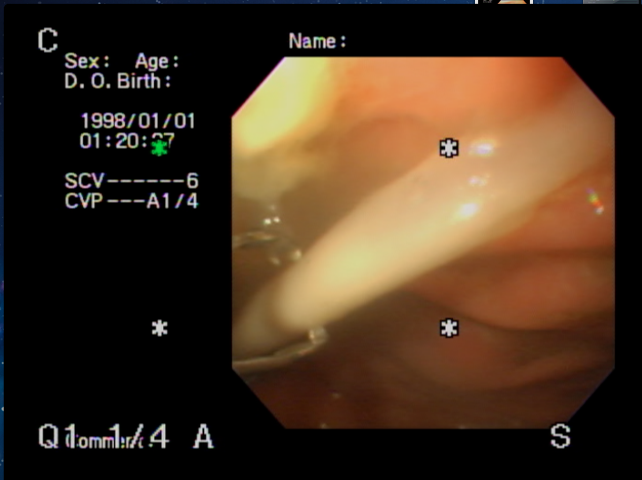

見つけてアームの照準を合わせて・・・

つかんで・・・(UFOキャッチャーの要領です)

そっと引き出しとりだします。 先端は消化され始め鋭利になっていて、そのままにすると胃の中を傷つける恐れが… 無事全て取り出し、事なきをえました。 わんちゃんにとっては骨付きのお肉はごちそうに見えます。 皆さん是非ご注意下さい。